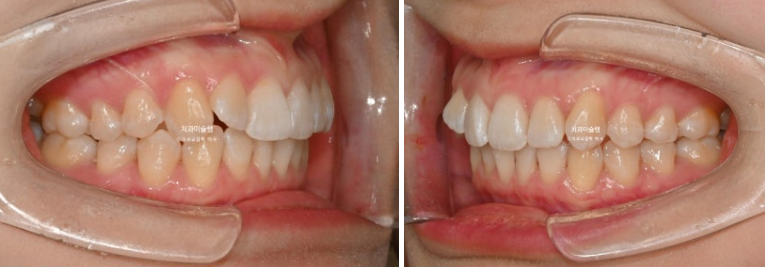

2급 교합관계를 보이는 좌측엔 교합관계 개선을 위한 악간고무줄 처방을 해서 덧니뿐아니라 교합관계개선과 주심선 개선을 도모합니다.

고무줄을 열심히 껴준 탓에 좌측 교홥관계는 좀 더 1급에 가까워졌습니다.

우측은 완벽한 1급을 달성했습니다